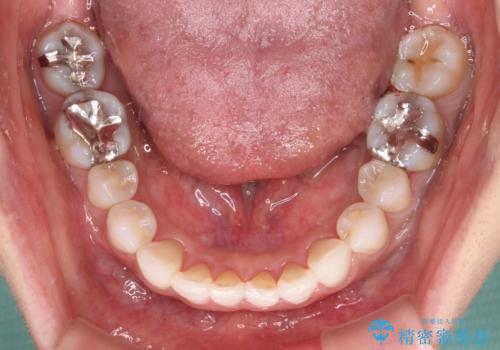

- 前歯のデコボコを気にして来院された患者様です。

歯列不正が軽度であり、インビザラインの装着時間を遵守してくださったため、日本と海外を行き来しながらも2年弱でしっかりと仕上げることができました。